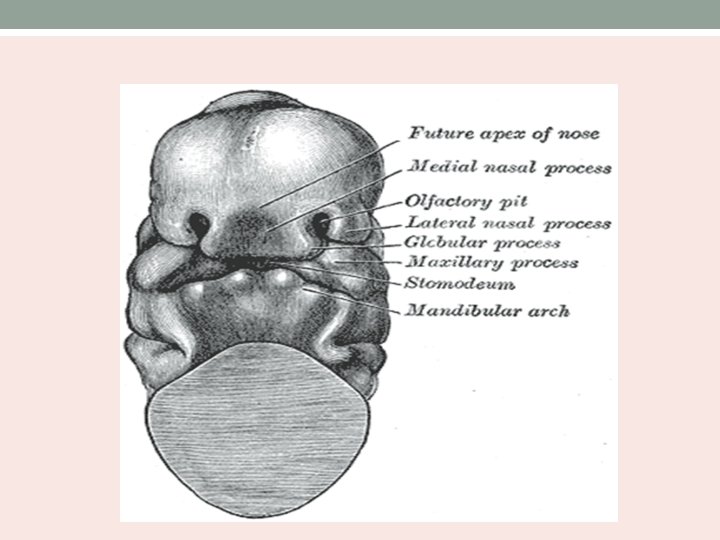

Embryology • Nasal cavity is first seen as nasal placode in the 4 th week of intrauterine life. • It is the thickening of ectoderm above the stomodeum. • Stomodeum is surrounded by superiorly – frontonasal prominence laterally – maxillary processes inferiorly – mandibular processes

• The placode thickens and sinks into the mesenchymal tissue – olfactory pit. • Lies between the proliferating medial and lateral prominences of frontonasal process. • Medial prominences fuse to form central portion of upper lip, premaxilla and primitive nasal septum. • The primitive nasal cavity and mouth are separated by bucco nasal membrane.